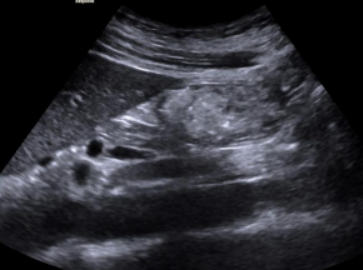

1. 胃窦为圆形或椭圆形且小而空的环状结构,形似“牛眼(图3), 宜评判为空腹。

图片

3  空腹,形似“牛眼